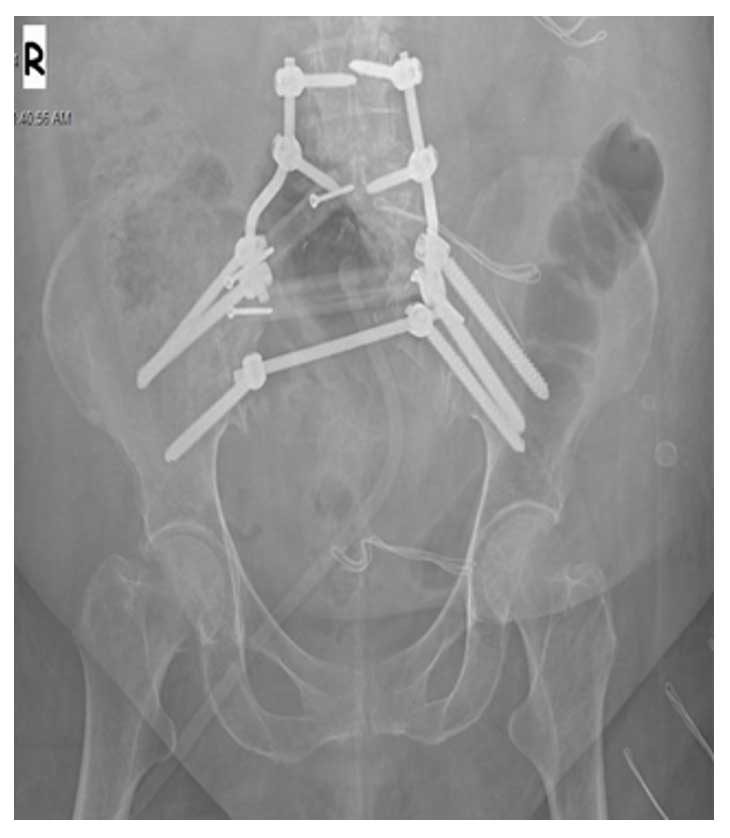

Hastaya sakrum sağ yarısındaki tümör tek parça halinde temiz sınırlar ile çıkarılmış (Sakrektomi), oluşan boşluk lumbopelvik fiksasyon ve fibula grefti ile yeniden yapılandırılmıştır.

Ameliyat Sonrası: Röntgende fibula ve lumbopelvik fiksasyon ile yapılan rekonstrüksiyon görülmekte .